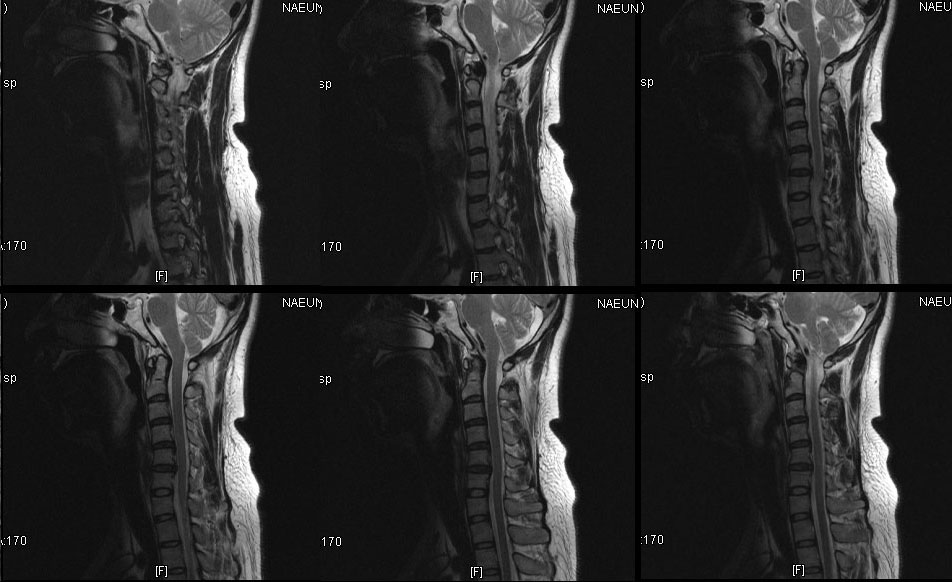

ֵ# ֹǰ (2009-03-02 16:43:47) (ֹȣ : b2b65e09702f ) ǰ ܰ ǰ : ְ ü㺣 2 Ʈ 160ȣ*140ȣ 2(20%) ֵ# (ID : g199co) ó Tel: 010-8754-@@@6 E-mail choidueckho@daum.net ּ ȣ : 000-000 : @6 5@@-59 @ Ž / Ȥ 6 . (MRI Ͽ) -------------ȸԳԴϴ.------------- , ü Ư Ű 171 Cm ü 84 Kg 33 ȯ ǥغ ôĸε Ǵ ġȿ ū ϼŵ ϴ. ش Ͻø 㿡 ˴ϴ. ǥغ Ӹ ƴ϶ , , Ϗ ٸ Ͽ Ʒ شȯ ȣ˴ϴ. Ư ǥ ǥõ 10 ̳ ų ּȭ ˴ϴ. ǥ ǥõ ȯ̳ ð~ ̳ ȿ ֽϴ. ȯںе鲲 ϰ ü ǥغ ϸ鼭 ȯ ȣ ġ ִ Ȯϰ ֽϴ. ٸ ε ȯ ġϰų ġῡ Ǵ ôĻ· Ÿ μ Ÿ ִ Դϴ. ġᳪ ߹ Ͻô شǴ Ʒ ϼ. IJϰ üũϽø 㿡 ˴ϴ. 1C~7C شǴ () ºҷ Ÿ ֽϴ. 1C.ھ, 1C.ں, 4C.5C.ھ, հ ̳ , 5C.ھ , 5C.6C.ڰ հ ̳ 6C.ڸ , 6C. κ Ḳ , 6C.ھ Ḳ , 6C.ڻ , ̳ ٸ ô߿ õ ȯԴϴ. ܵ ȯ ִٸ شǴ Ī ϼ. ĿCڸ(ĸ), ǥغ Ͻô Ͽ ߰ մϴ. Ͽ ġḦ Ͽ ũ(߰Ż)ġ, հ , ġ, , Ḳ ġ Ǵ ġ |